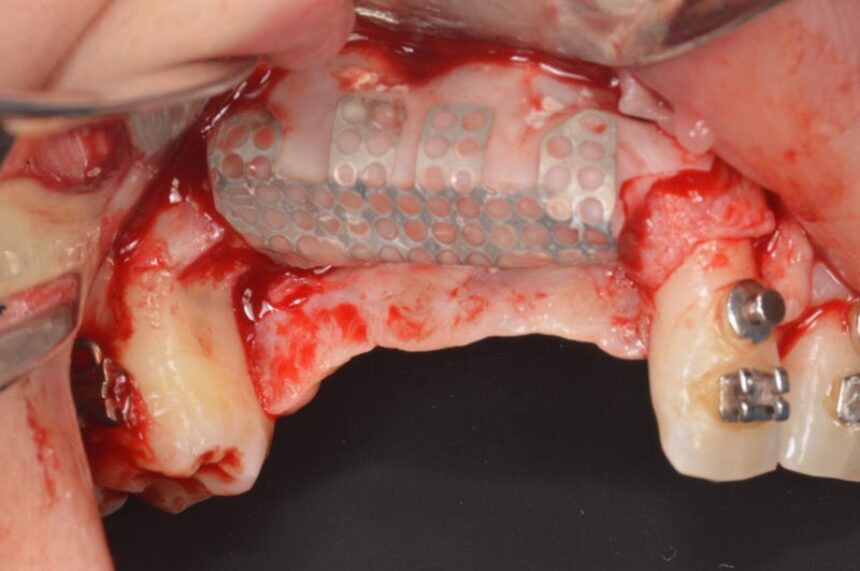

Πιο συγκεκριμένα, ο Prof. Massimo Simion, είναι ένας από τους πρωτεργάτες της διαδικασίας της Κατευθυνόμενης Οστικής Αναγέννησης στο χώρο της εμφυτευματολογίας. Μέσα από την τριαντακοετή εμπειρία του θα μας μεταφέρει τις εμπειρίες του στο χώρο αυτό καθώς και τα μυστικά επιτυχίας σε περιστατικά εκτενούς έλλειψης της φατνιακής ακρολοφίας τόσο στην άνω, όσο και στην κάτω γνάθο, αλλά και θα παρουσιάσει την αντιμετώπιση διαφόρων επιπλοκών που μπορεί να προκύψουν στην αντιμετώπιση αυτών των περιστατικών που αποτελούν πρόκληση για τους κλινικούς.

Η πλήρως νωδή κάτω γνάθος: διάφορες ατροφίες και αντίστοιχες χειρουργικές τεχνικές – Κοντά εμφυτεύματα - Οστικά μοσχεύματα – GBR

Οριζόντια και Κάθετη Αύξηση της Ακρολοφίας: χειρουργικό υπόβαθρο - χειρουργικές τεχνικές – απορροφήσιμες και μη-απορροφήσιμες μεμβράνες – λήψη οστικού μοσχεύματος από ενδο-στοματικά σημεία – βίντεο